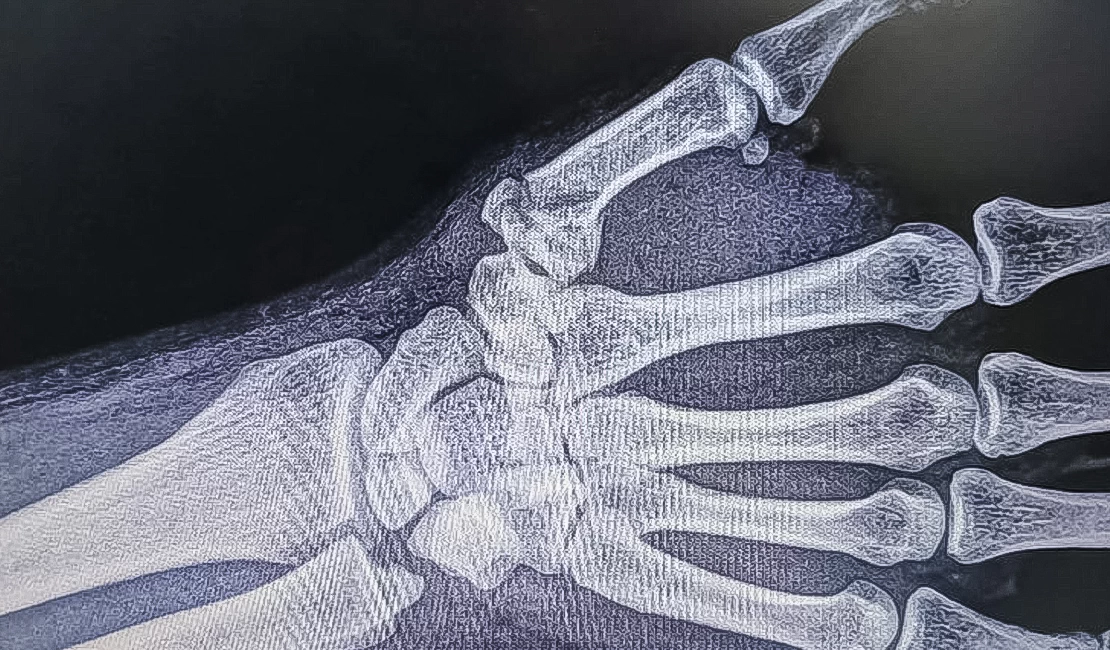

К специалисту обращаются в основном после травм

(например, после повреждений сухожилий опасным инструментом

или глубоких порезов ножом при приготовлении пищи),

а также при переломах, в том числе для установки

металлических фиксирующих конструкций или их удаления.

К специалисту обращаются в основном после травм

(например, после повреждений сухожилий опасным инструментом

или глубоких порезов ножом при приготовлении пищи),

а также при переломах, в том числе для установки

металлических фиксирующих конструкций или их удаления.